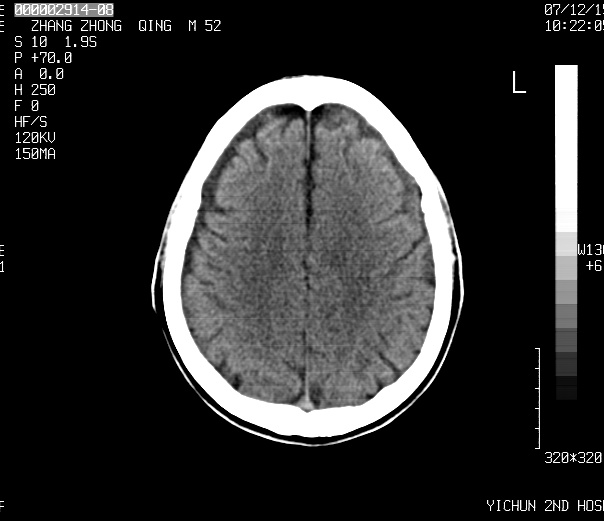

考虑    四叠体池脂肪瘤。脑萎缩

1)四叠体池脂肪瘤.2)脑萎缩.

2、脑萎缩。